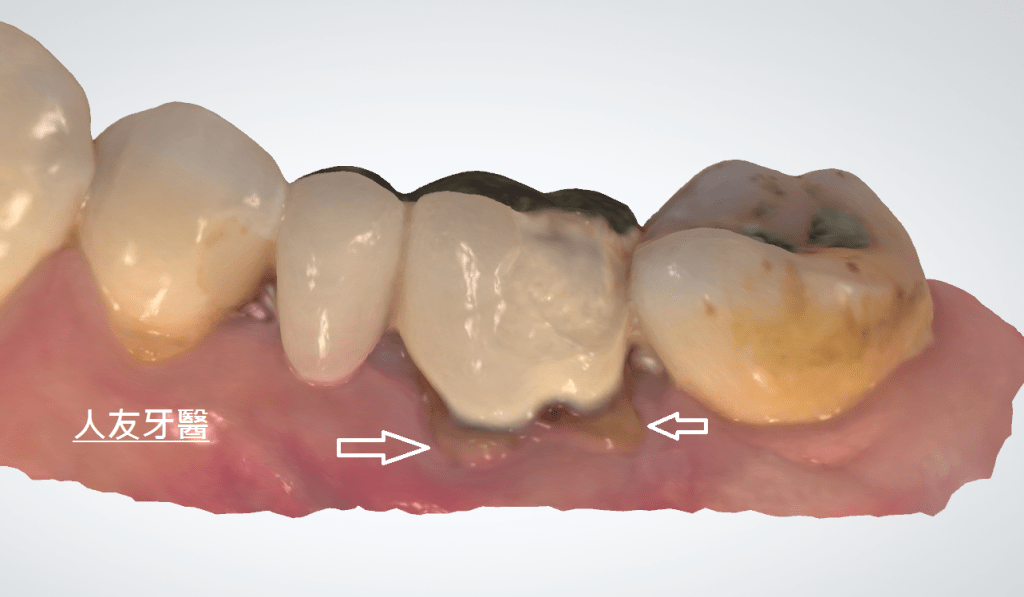

下圖是別家做的牙橋

想詢問周醫師如何處理。醫師看了X-RAY發現右邊側門牙紅色圓圈的地方有病變,有可能留不住。左邊側門牙藍色箭頭牙齒有裂到肉,也可能留不住。經過討論後建議都拔除。